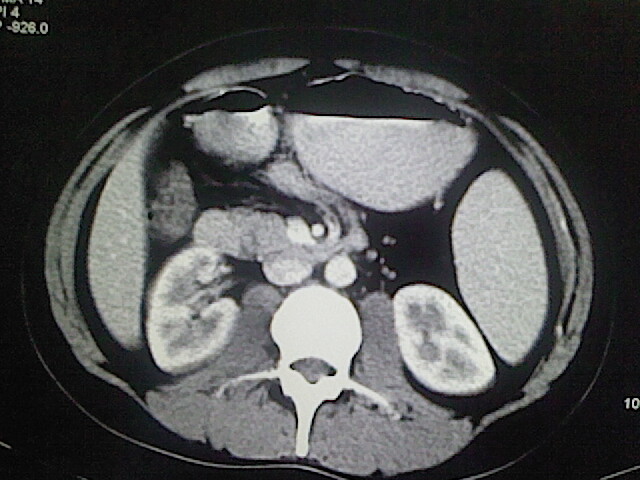

以下是引用卜一在2009-3-14 9:49:00的发言:[br]胆囊萎缩,胆囊壁不规则增厚,内部结构模糊,增强明显强化。另:肝左叶外侧段肝囊肿。支持:慢性胆囊炎!高度可疑:胆囊癌!

以下是引用余辉在2009-3-14 8:48:00的发言:[br]1)慢性胆囊炎。2)肝左叶外侧段肝囊肿。3)脂肪肝。[br]支持,胆囊萎缩,密度增高,不知b超具体有何提示,钙胆汁?结石?

以下是引用jiangjing在2009-3-14 10:18:00的发言:[br]1)慢性胆囊炎。2)肝左叶外侧段肝囊肿。3)脂肪肝。4.】建议行肝功能检查